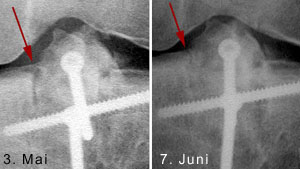

Röntgenkontrolle am 7. Juni

Immerhin scheinen meine Knochen eine Art Schnellheilungsmechanismus zu haben: Nur 5 Wochen nach der Korrekturoperation ist der Knochen schon fast wieder ganz verheilt - im folgenden Bild aus dem Inneren des Knies ist links das Bild vom 3. Mai, rechts jenes vom 7. Juni. Das versetzte Stück der Eminenz ist fast wieder fest drin; die Lücke beim Pfeil hat sich deutlich verkleinert - Krücken ade, Schmerzen leider noch nicht ganz. Das Streckdefizit beträgt immer noch 12 Grad.